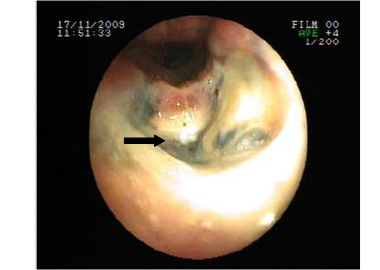

The posterior anterior chest graphy showed consolidation area in right paracardiac region. The high resolution thorax spiral computed tomography (HRCT) obtained on admission revealed consolidation area and atelectasis in right middle lobe (Figure 1). Flexible bronchoscopy (FOB) application was planned to the patient. FOB examination revealed hypervascularisation, hyperemia, deformed bronchial trees and these findings were similar to previous FOB findings. Previous FOB examination has been done to examine middle lobe atelectasis. However, white necrotic lesions were observed in orifice of the middle lobe and at entry of main right bronchus and intermediate bronchus differently from previous bronchoscopic examination (Figure 2, 4). Biopsy from necrotic lesions and bronchus lavage were performed. Histological and cytological findings of material were benign. Microscopic findings of biopsy revealed infection that consists of concentrated lymphoplasmocytes, regular cartilage, and a few polymorph nuclear leucocytes. No AFB was performed on the biopsy specimen. AFB was negative in bronchus lavage; however, mycobacterial cultivation was positive revealing mycobacterium tuberculosis and sensitive to all major tuberculosis agents.

Figure 2

Necrosis and anthracosis in orophis of the middle lobe